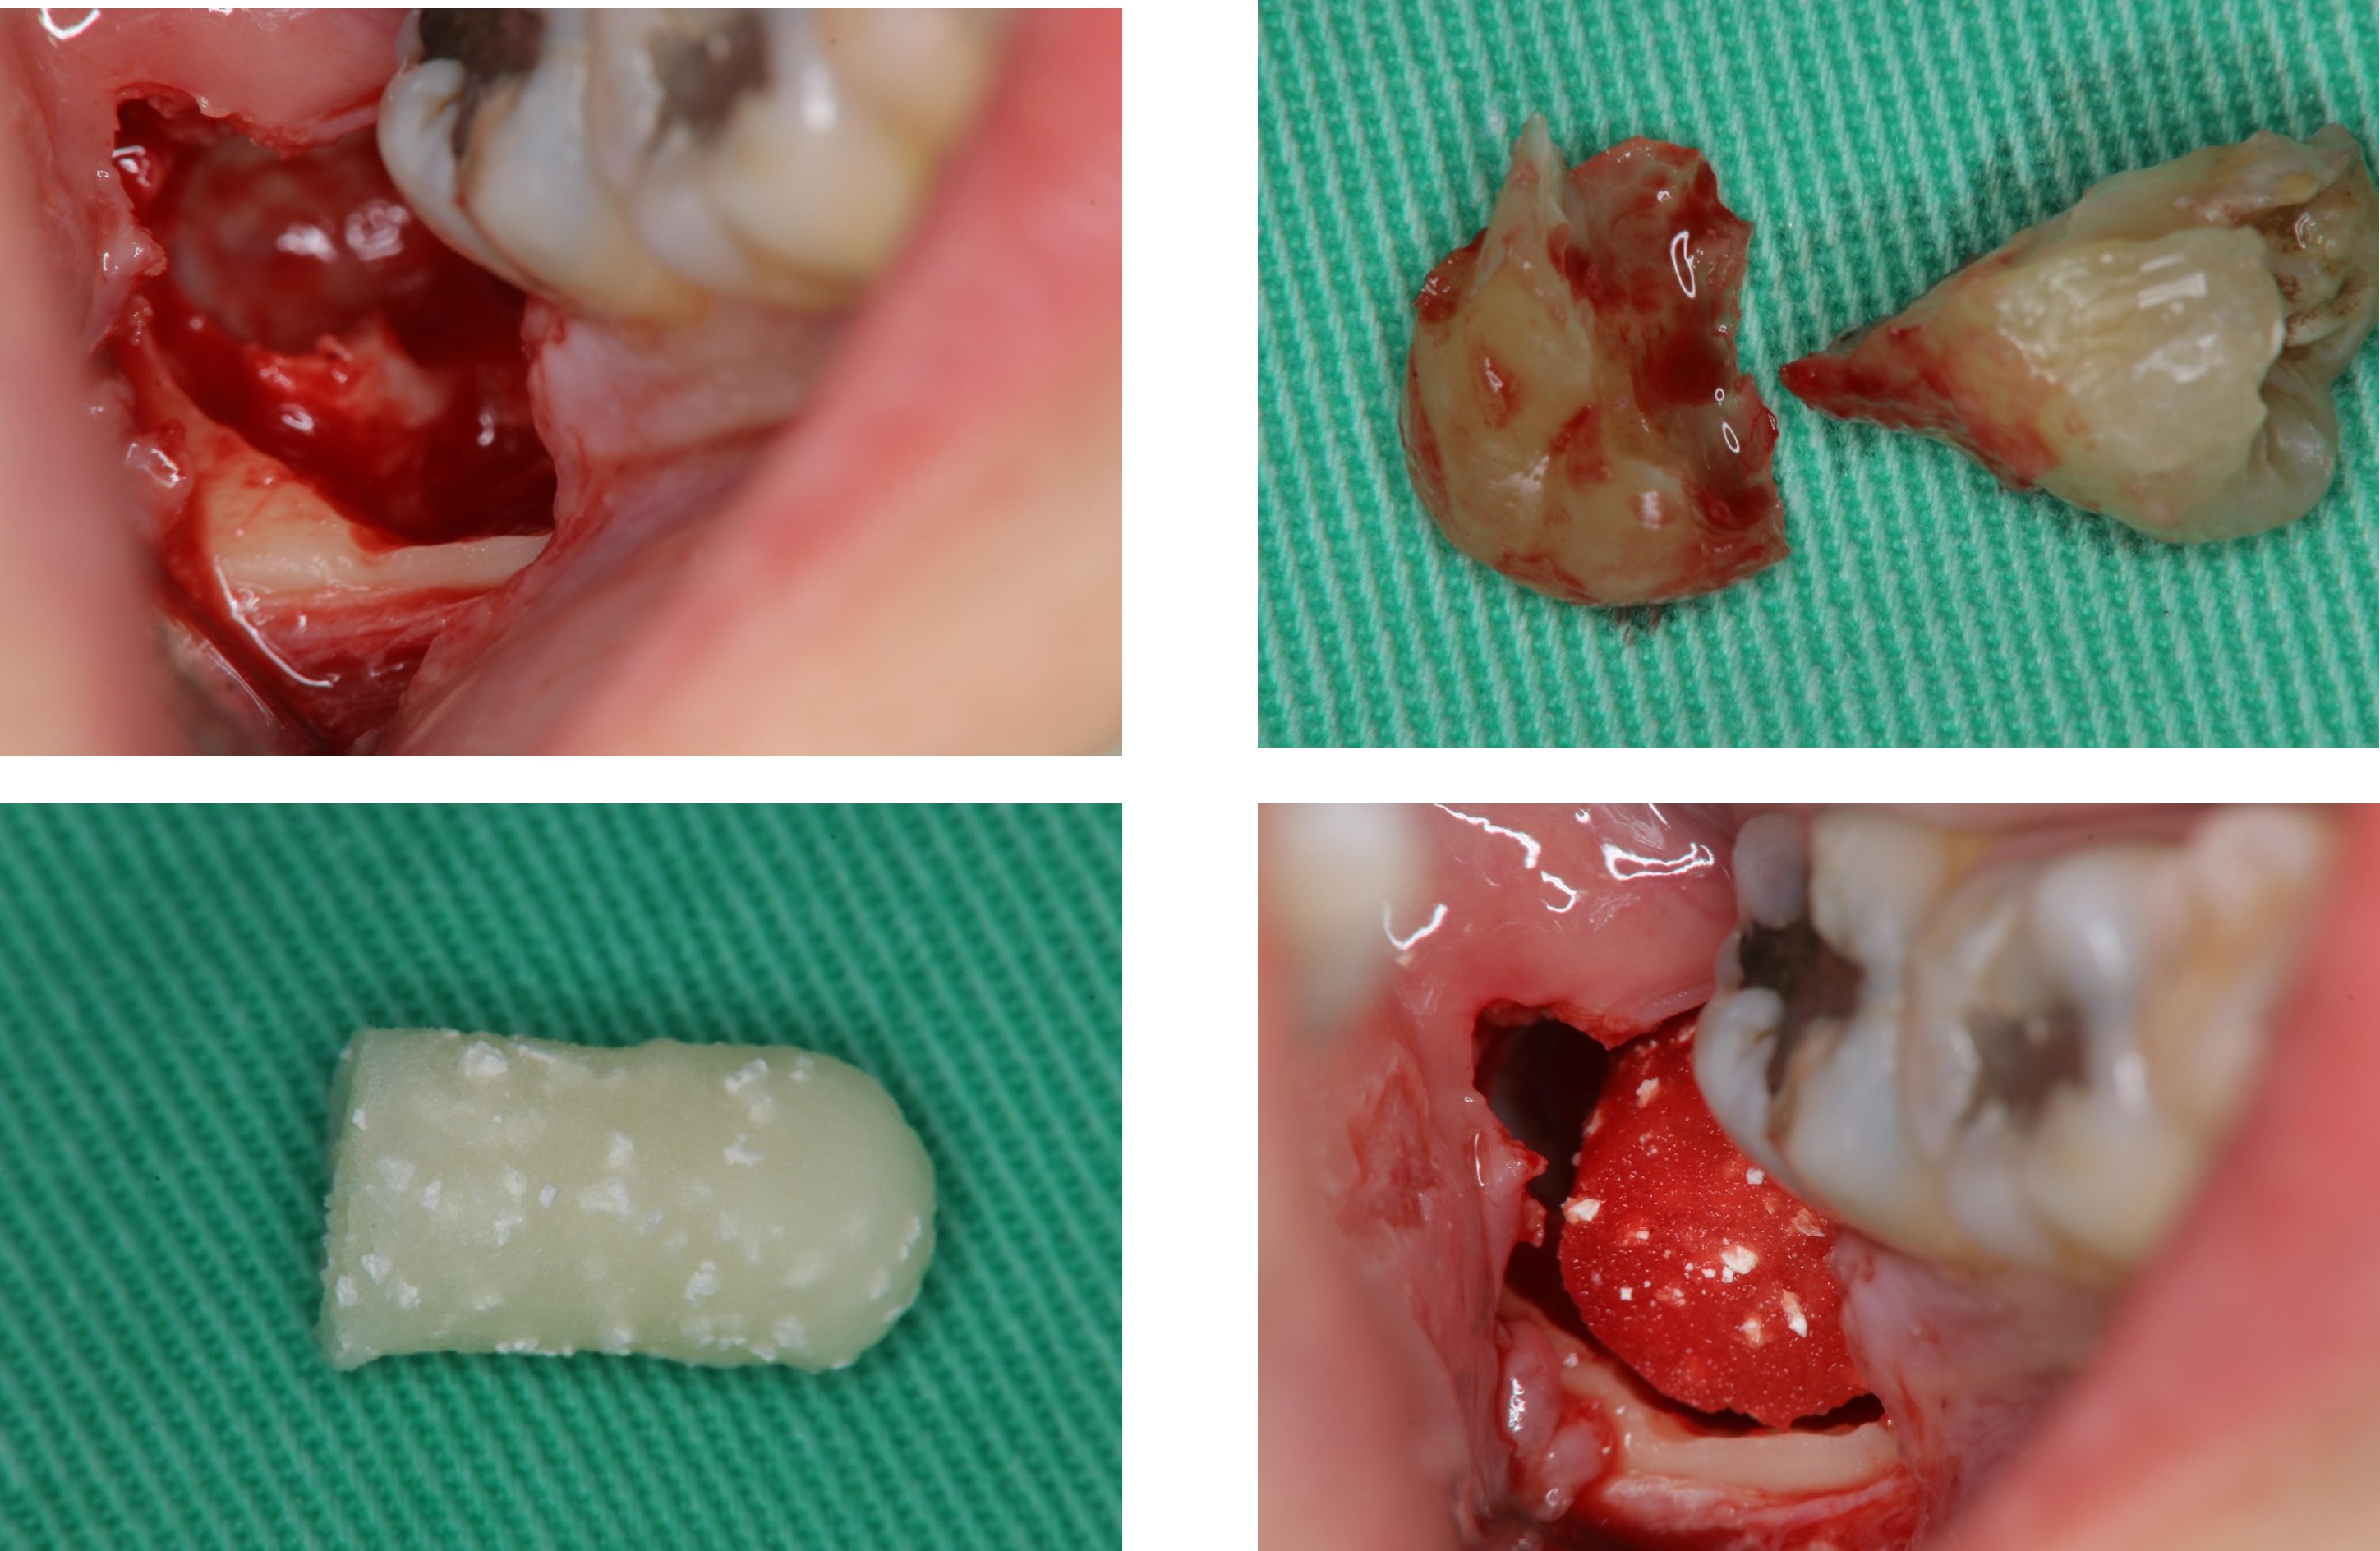

1週後傷口癒合良好

術前、術後比較

使用骨質增生膠原蛋白,來處理拔牙後的傷口。此材料適用的範圍不僅用於拔牙後傷口,所有顎骨中的病灶於手術後皆建議使用。